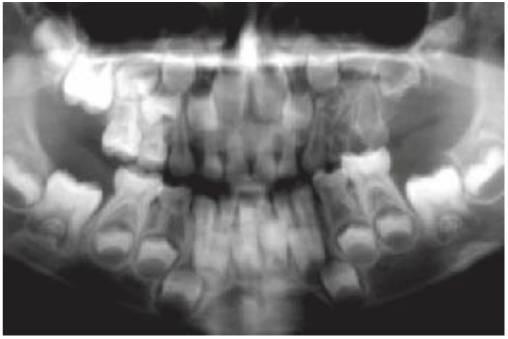

- Varios dientes ausentes (fig. 9.1 B).

Los dientes son pequeños y cónicos y a menudo presentan un gran diastema anterior (fig. 9.3). Sus manifestaciones pueden limitarse a un solo diente ausente o a un incisivo lateral en clavija (v. hipótesis de Lyon, más adelante) y las mujeres heterocigóticas suelen ser diagnosticadas gracias a este tipo de dentición.

Dentro del grupo de displasias ectodérmicas, se observan asimismo modos de herencia autosómica tanto dominante como recesiva. Si se compara con la displasia ectodérmica hipohidrótica ligada al cromosoma X, en las familias con este trastorno no existen diferencias tan acentuadas en cuanto al grado de trastorno entre los hombres y las mujeres (figs. 9.2A, 9.4). Se han identificado mutaciones en el gen MSX1 (4p16.1) en familias con terceros molares y segundos premolares ausentes con o sin paladar hendido/labio leporino, así como en familias con el síndrome diente-uña (Witkop). Se han observado mutaciones del gen PAX9 (14q12-q13) en otras familias con dientes ausentes de forma autosómica dominante.